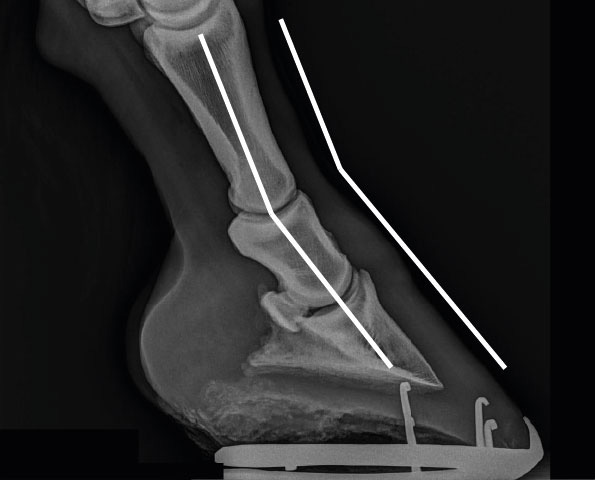

Röntgenbild eines Hufes mit nach hinten gebrochener Huf-Fessel-Achse, einer kleinen Streckung im Krongelenk, einer kleinen Beugung im Hufgelenk und einem etwas verbreiterten Hufbeinträger

Röntgenbild eines Hufes mit nach hinten gebrochener Huf-Fessel-Achse, einer kleinen Streckung im Krongelenk, einer kleinen Beugung im Hufgelenk und einem etwas verbreiterten Hufbeinträger.

Ergänzend zur Illustration zeigt die folgende Röntgenaufnahme eine Beugung des Hufgelenks, die Ursache der Beugung ist hier allerdings nicht erkennbar. Das intakte Strahlbein spricht allerdings für eine angeborene Beugung.

Röntgenbild eines Hufes mit nach vorne gebrochener Huf-Fessel-Achse und einer Beugung des Hufgelenks

Röntgenbild eines Hufes mit nach vorne gebrochener Huf-Fessel-Achse und einer Beugung des Hufgelenks.